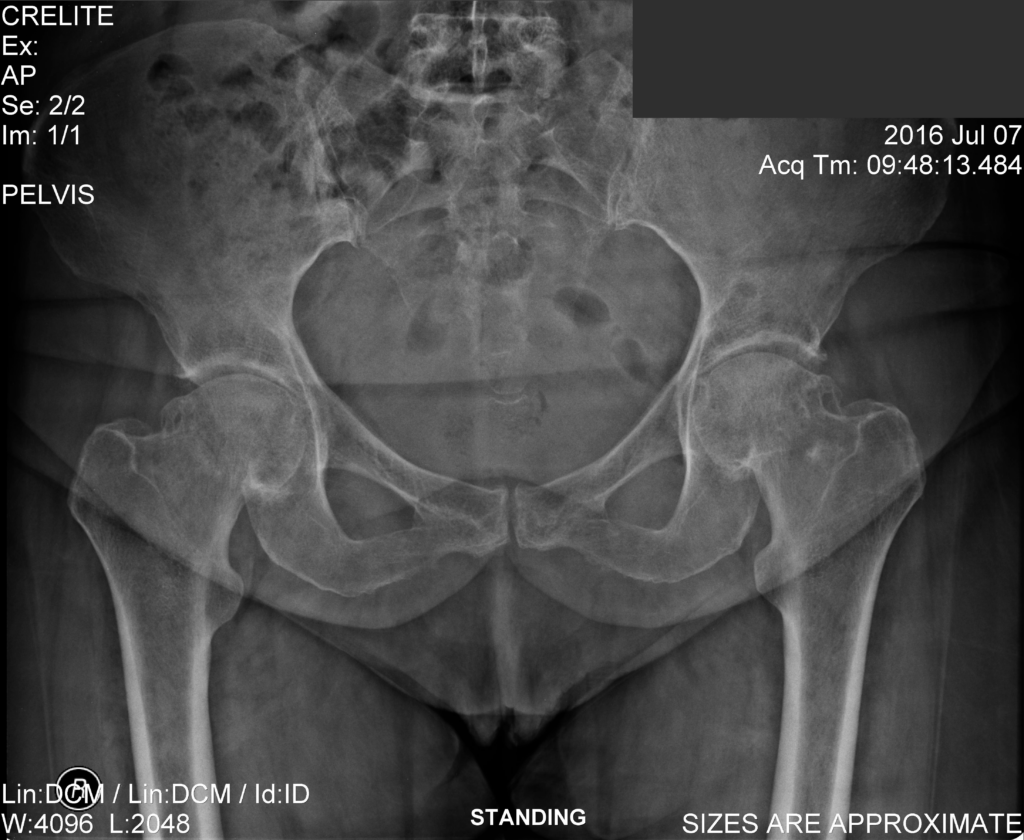

Ακτινογραφίες ασθενή ΠΡΙΝ την επέμβαση αμφοτερόπλευρης αρθροπλαστικής ισχίων